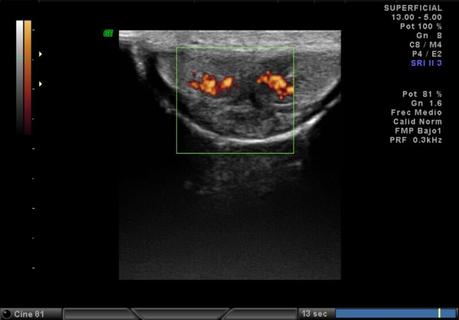

Se realiza ultrasonido en escala de grises con aplicación Doppler color con transductor lineal multifrecuencia en tiempo real observando los siguientes hallazgos:

Trayectos vasculares conservados.